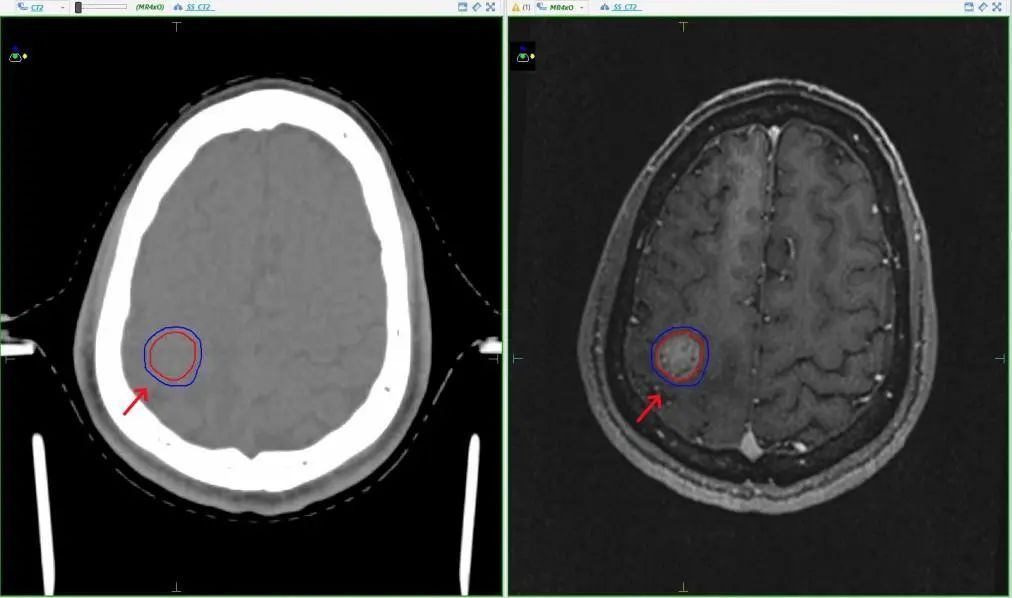

2025 年 5 月,他无意中发现右侧锁骨上窝出现约 2cm 肿物,确诊为淋巴结转移癌。更令人揪心的是,6月8日颅脑 MR 增强检查显示,他的右侧颅内出现大小约 19mm×15mm 的新增结节,考虑为转移瘤。至此,刘先生的病情已发展至晚期,且出现脑转移,频繁的头痛与肢体无力严重影响其生活质量,生命健康遭受巨大威胁。

▲MR检查显示张先生存在肺癌脑转移

在治疗过程中,肿瘤放射治疗团队基于定位CT与MR影像融合,对刘先生脑内19mm的转移病灶进行精准定位与分析,于6月10日完成定位制膜。

精准定位:采用热塑膜固定头部,CT/MRI影像融合重建三维靶区;